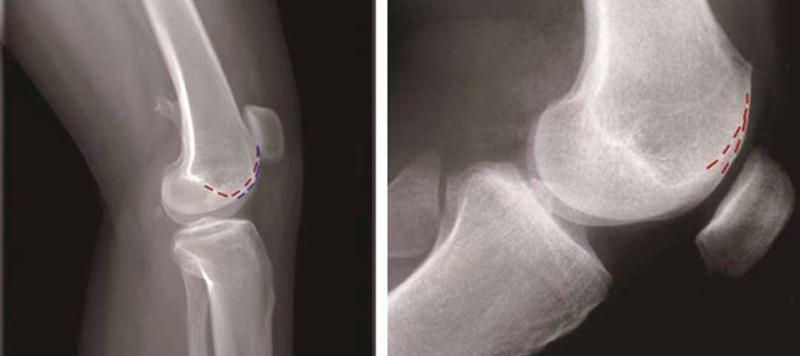

①交叉征:

H.Dejour在1987年介绍了股骨滑车发育不良在膝关节标准侧位X线片的特殊表现,描述了交叉征(crossing sign)。在股骨滑车发育不良的膝关节标准侧位像上,股骨滑车沟基底线会与股骨外髁的轮廓线相交叉,即为交叉征(图11),意味着股骨滑车发育平坦。

图11 交叉征